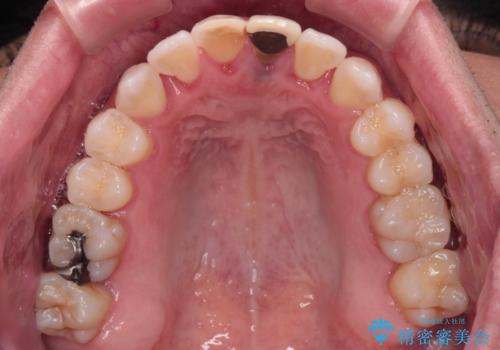

- 他院でインビザラインによる矯正治療を行っているものの、前歯の変色が気になるとのことで来院された患者様です。

インビザラインでの矯正治療がそろそろ終了とのことで、新しいインビザラインセットを発注する前に気になっている前歯2本をオールセラミッククラウンにて補綴治療を行うこととしました。

歯肉の腫脹が認められたため、仮歯へ置き換える過程で腫脹改善の指導などを行い、よりよい状態で治療を行うこととしました。